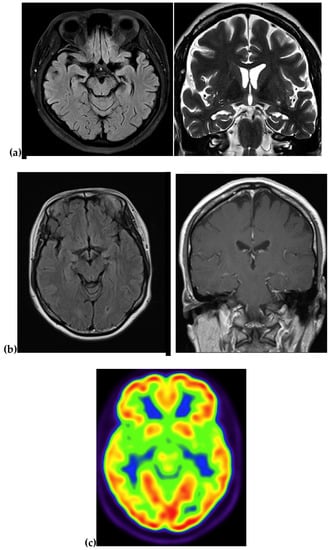

| Imaging | Atrophy and fronto-parieto-temporal enlargement of cortical sulci | NA | NA | MRI: atrophy in the right temporal and parietal regions PET: NA | MRI: Atrophy in the medial region PET: reduced metabolism in temporal and parietal region |